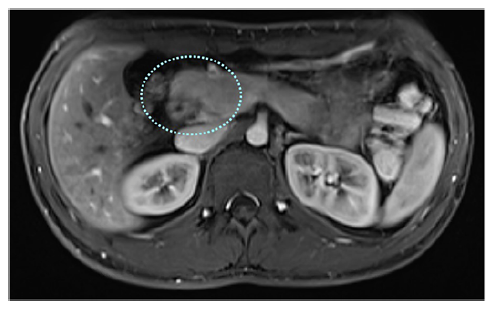

These imaging findings suggested gastric outlet obstruction secondary to incomplete annular pancreas (AP). Magnetic resonance imaging/cholangiopancreatography confirmed the diagnosis, showing the characteristic “crocodile jaw” appearance of the pancreatic head (Fig. 3). The remainder of the pancreas exhibited normal morphology, with no signs of focal or diffuse injury or ductal ectasia. After multidisciplinary discussion, the patient underwent a Roux-en-Y gastrojejunostomy, was discharged after 7 days, and reported no further complaints during follow-up.

Fig. 3 MRI scan with “crocodile jaw” appearance of the pancreatic head (dotted blue circle). MRI, magnetic resonance imaging.